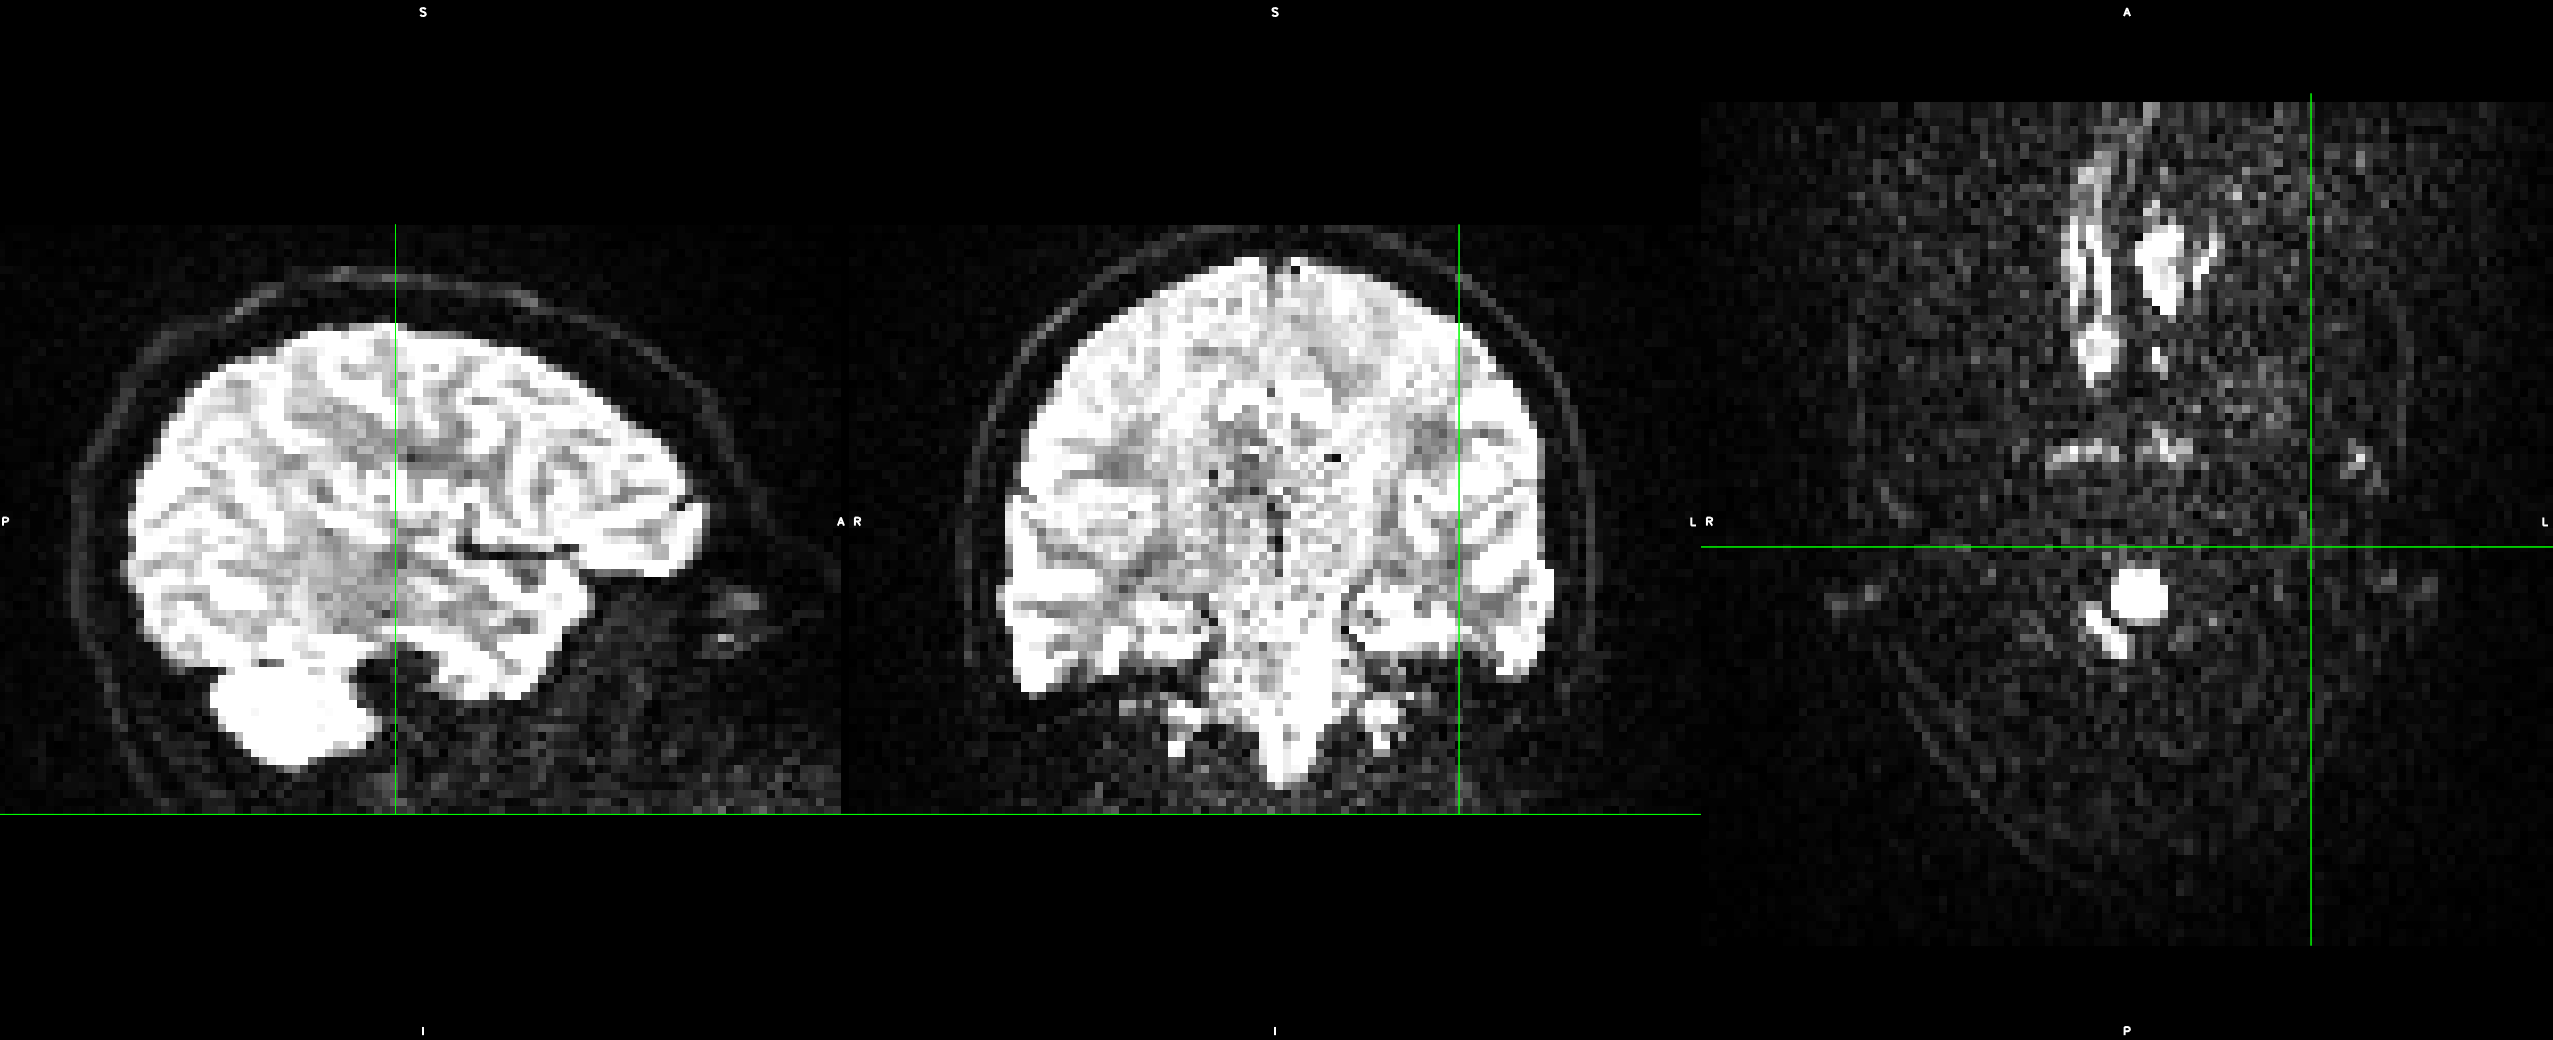

Subject movement correction and B-matrix reorientation are done using the freely available FSL tools jenkinson2002improved and the DIPY imaging library garyfallidis2014dipy , respectively. A practically relevant implementation detail concerns boundary effects. As illustrated in Figure 5, missing information can enter the field of view when applying image transformations. We found that q-space inpainting near the boundary of the domain works more reliably if we resolve these cases with nearest neighbor extrapolation, rather than with zero padding.

From these datasets, we use the five non-diffusion weighted () MRI scans each, as well as 30 diffusion weighted images (, diffusion gradient duration , spacing ). Each image consists of voxels with a resolution of . The data, and the effects of subject motion, are illustrated in Figure 6.

It can be seen in Figure 6 that subject motion during different phases of the acquisition leads to different types of artifacts. Results in Table 1 include the motion correction described in Section 3.3, which compensates spatial misalignments of different scans. However, motion can also lead to signal dropouts or to distortions within scans, which our current codec does not explicitly account for. This explains why q-space inpainting is less effective on the second as compared to the first scan. However, even on this challenging dataset that exhibits unusually strong artifacts, q-space inpainting still provides a benefit compared to all other alternatives.